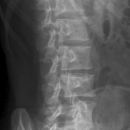

Lendenwirbelsäule lateral

Indikation

Fraktur und degenerative Veränderungen, Skoliose

Lagerung

exakte Seitenlage

Arme nach vorn oben,

Beine angewinkelt und 45° zwischen die Knie

evtl. einen 15° Keil unter Taille zum WS- Ausgleich

Zentralstrahl

ZS senkrecht auf Objekt- und Detektormitte

Quer: 2 QF über Beckenkamm

Längs: an QZ von den Dornfortsätzen 4 QF nach ventral

Bemerkung

möglichst bei Atemanhalten - Exspiration

auch im Stehen möglich (orthopädisch)

Qualitätskriterien

Rein seitliche Darstellung der Lendenwirbelsäule einschließlich ihrer Dornfortsätze mit 12. Brustwirbel und lumbosacralem Übergang.